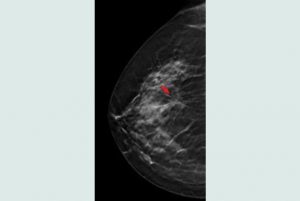

Mehr erfahren zu: "Verbesserte Diagnostik bei Brustbiopsien" Verbesserte Diagnostik bei Brustbiopsien Gewebeproben können mit neuem System präziser und schneller entnommen werden